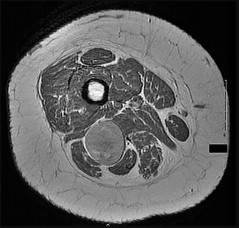

This patient has a dedifferentiated liposarcoma within a preexisting atypical lipomatous tumor. The imaging demonstrates a large fatty mass with increased internal septations proximally (the atypical lipomatous tumor) and a solid enhancing mass distally (the dedifferentiated portion). A biopsy reveals a high-grade liposarcoma. The other diagnostic responses do not reflect sarcomatous transformation of the lesion.

Surgical treatment of a high-grade sarcoma involves wide surgical resection. Radiation decreases local recurrence but does not clearly influence overall survival. The role of chemotherapy in high-grade soft-tissue sarcomas remains investigational; there is a modest (8%-15%) associated improvement in overall survival.

Intramuscular lipomas and atypical lipomatous tumors are treated with marginal resection alone. Radiation therapy for soft-tissue sarcomas may be given before or after surgery. When administered before surgery, patients have a higher wound complication rate but better long-term function attributable to lower rates of lymphedema, fibrosis, and contractures.